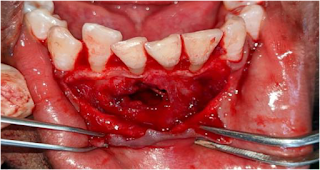

In the present case surgery was done on lower anterior teeth.

Tissue reflection should begin from the vertical releasing incision at the junction of the submucosa and the attached gingiva. After the tissue is reflected, it must be retracted to provide adequate access for bone removal and root-end procedures. Removal of cortical bone to expose the root apex. currettage os done to remove cyst and lining.

The root has a darker, yellowish color and is hard, whereas the bone is white, soft, and bleeds when scrapped with a probe.